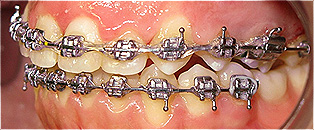

Apinhamento dentário com os dentes caninos em desoclusão (classe II, divisão 2).

![]() |

Após dois anos de tratamento ortodôntico.